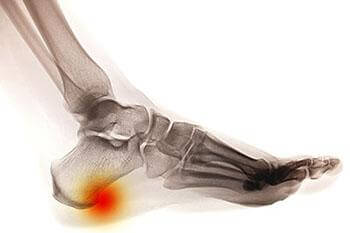

Heel Spurs

heel spur

A heel spur takes the form of a bony-like growth. This is due to a calcium deposit that extends between the heel bone and foot arch. They can grow up to half an inch in length; however, they may not be outwardly visible. Because heel spurs tend to grow, increasing the overall discomfort felt, it’s important that you seek professional help as soon as pain is experienced for early detection.